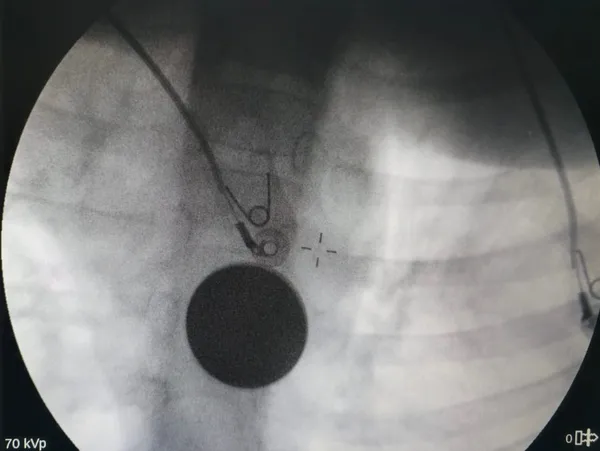

Edinilen bilgilere göre, yabancı cisim yutma şikâyetiyle hastaneye başvuran küçük hasta, yapılan ilk değerlendirme ve görüntüleme tetkiklerinin ardından ilgili branşlar tarafından operasyona alındı. Y.K.'nin yemek borusuna kadar ilerlediği tespit edilen madeni paranın çıkarılması için Gastroenteroloji Uzmanı Dr. Yaren Dirik ile Kulak Burun Boğaz (KBB) Hekimi Dr. Yasin Gökçınar tarafından ortak bir girişim gerçekleştirildi.

Siirt Eğitim ve Araştırma Hastanesi Başhekim Yardımcısı Uzman Dr. Burak Özkan, konuya ilişkin yaptığı açıklamada çocuk hastalarda yabancı cisim yutma vakalarının ciddi riskler oluşturabileceğine dikkat çekerek, "Hastanemize başvuran 8 yaşındaki hastamızın yemek borusuna kaçan madeni para, gastroenteroloji ve KBB ekiplerimizin koordineli ve titiz çalışmasıyla herhangi bir komplikasyona yol açmadan başarılı bir şekilde çıkarılmıştır. Operasyon süreci sorunsuz geçmiş olup hastamızın genel durumu iyidir," ifadelerini kullandı. Operasyonun ardından bir süre gözlem altında tutulan Y.K.'nin tedavisinin tamamlandığı, genel sağlık durumunun iyi olduğu ve herhangi bir ek probleme rastlanmadığı bildirildi. Küçük hasta, gerekli kontrollerin ardından sağlıklı bir şekilde taburcu edildi.